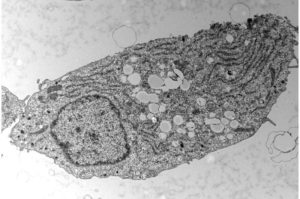

(Diabete di tipo 2-Immagine: cellula beta pancreatica al microscopio elettronico. I cerchi bianchi visibili al centro della cellula corrispondono a goccioline di accumulo di grasso. Credito: © UNIGE – laboratorio Maechler). Con quasi il 10% della popolazione mondiale colpita, il diabete di tipo 2 è un grave problema di salute pubblica. Uno stile di vita eccessivamente sedentario e […]